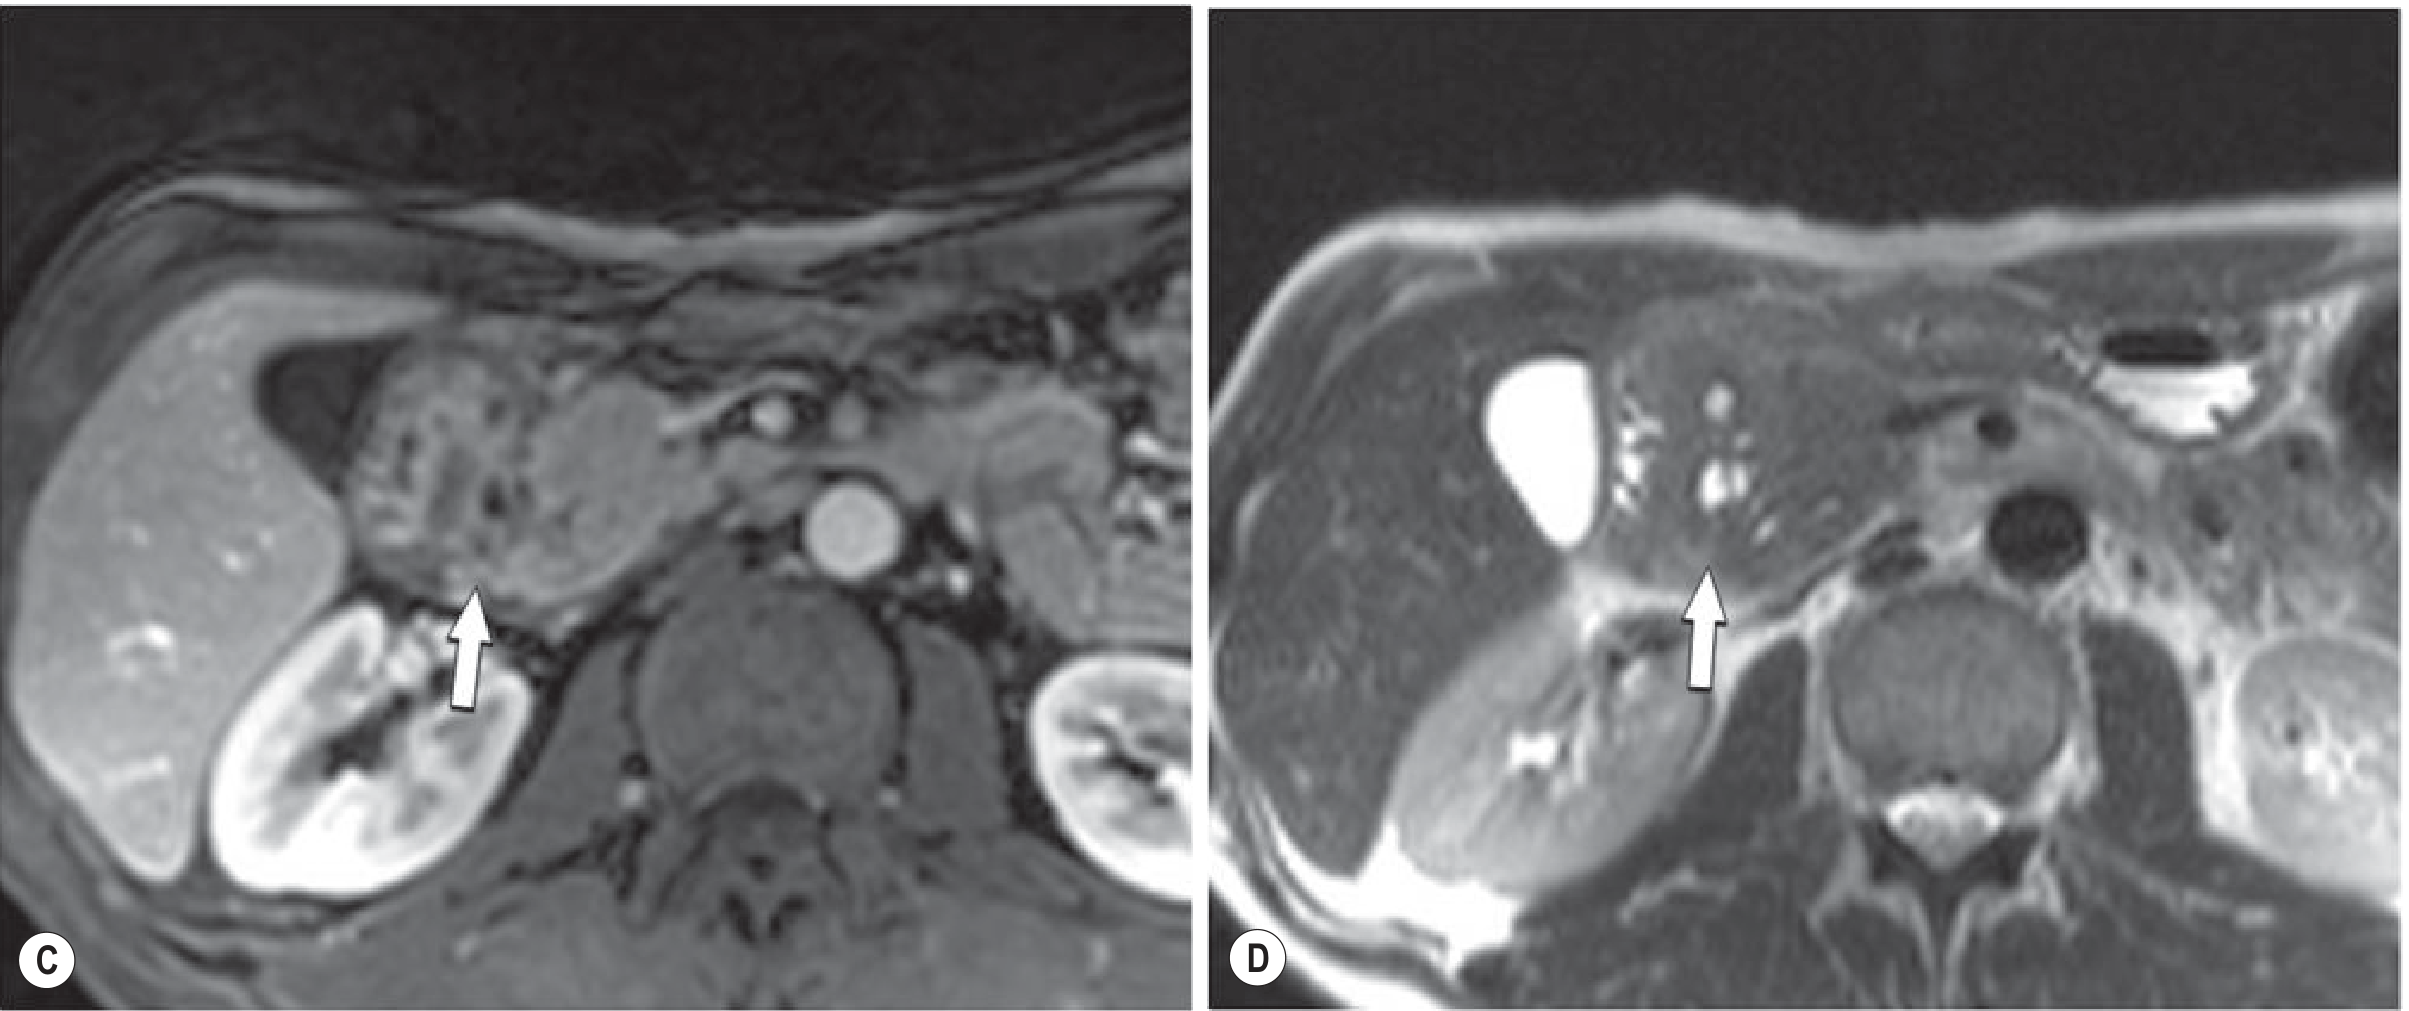

Fig. 25.23 C-D (Grainger & Allison's) — Gadolinium-enhanced T1 shows hypovascular groove mass (C, arrow); T2 shows the characteristic cysts (D, arrow):

MRI of paraduodenal pancreatitis — T1 hypovascular mass and T2 cysts

• Pathognomonic cystic changes within the lesion on T2-weighted imaging (see Fig. 25.23 D below)

• MRCP is important in the workup — shows both the hypovascular lesion and the cysts

Fig. 25.23 (Grainger & Allison's) — MRI demonstrating the hypovascular groove mass (C) with the characteristic T2 cystic changes (D, arrow):

MRI of paraduodenal pancreatitis showing hypovascular mass and T2 cysts